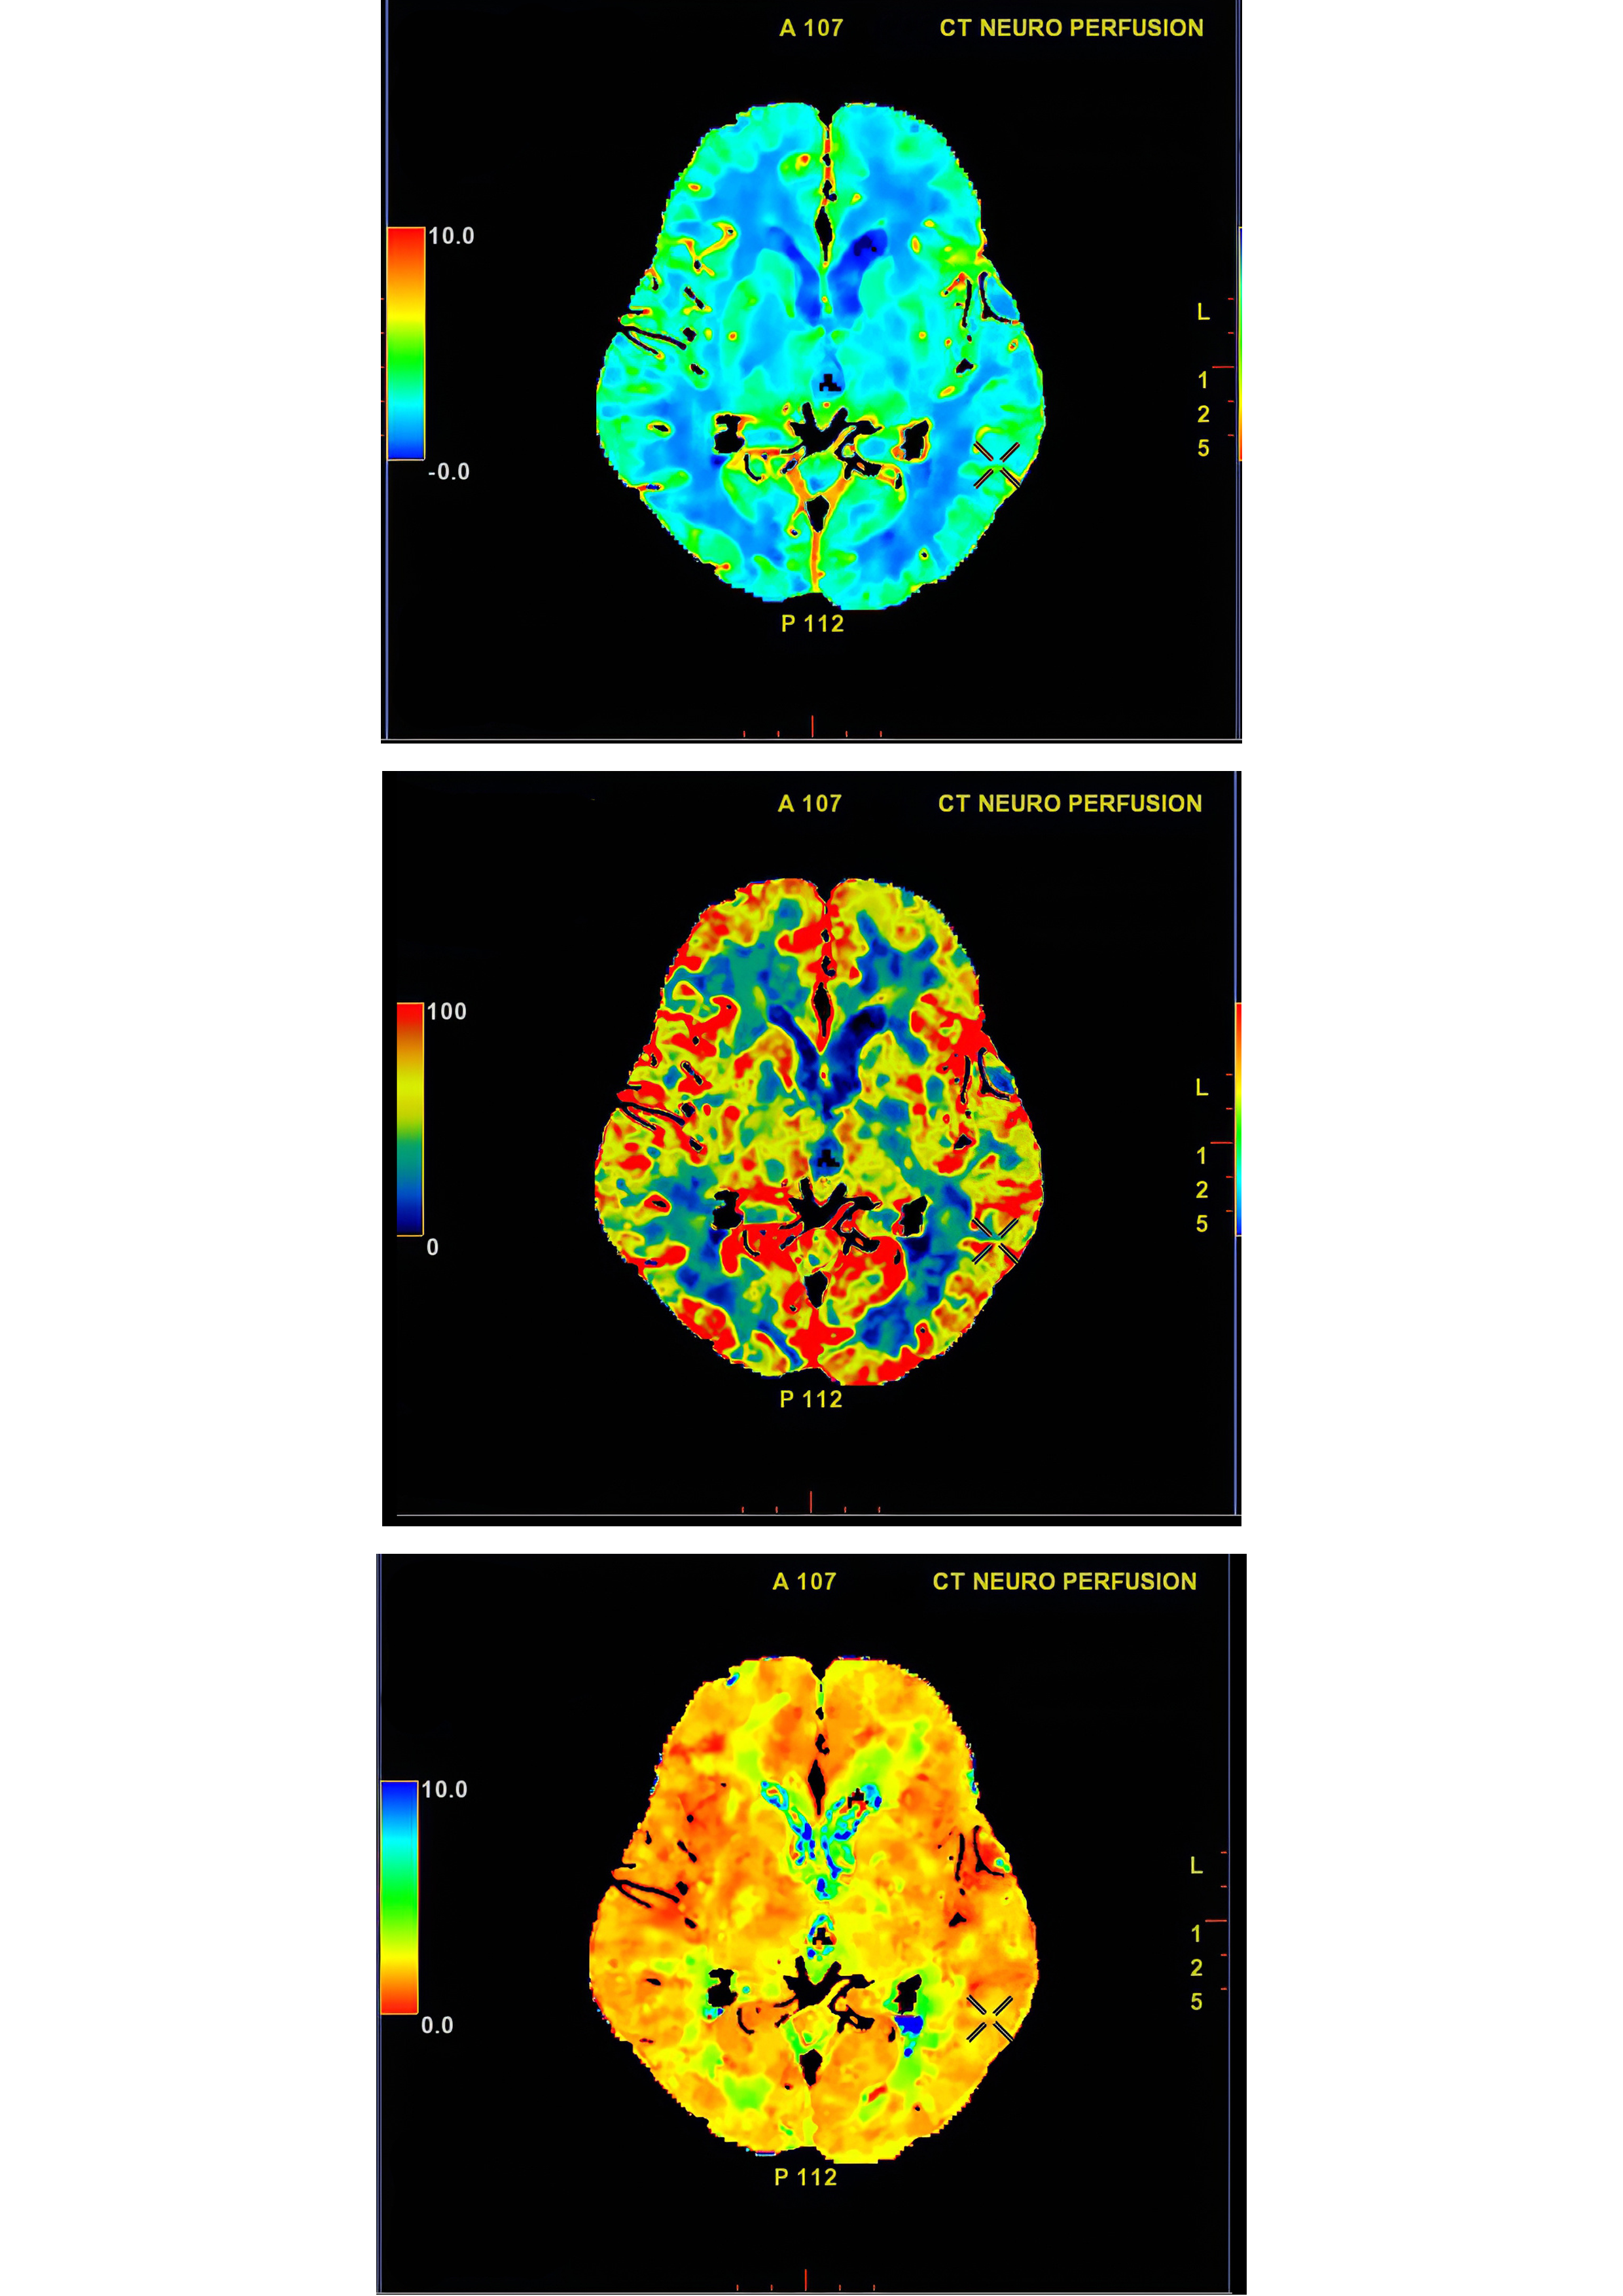

La neurociencia y la neurotecnología están en rápida evolución, logrando avances significativos que han facilitado una mejor comprensión del funcionamiento cerebral. Estos campos han dado lugar a nuevas tecnologías, como las avanzadas técnicas de imagen cerebral, que permiten a los científicos observar el cerebro en acción y entender cómo se procesa la información y se toman decisiones. A través de herramientas como la resonancia magnética funcional (fMRI), se han estudiado diversas enfermedades y trastornos, desde la depresión hasta el Alzheimer, ampliando notablemente el conocimiento en estas áreas.